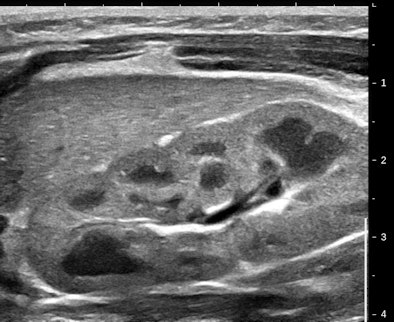

Figures 2A and 2B are cropped B-mode and simultaneous SWE of an 8-mm nodule in an isolated island of parenchyma in the upper outer quadrant of a 43-year-old woman.

| Figures 2A and 2B. |

The B-mode features are very abnormal, at the least BI-RADS 4. The elastogram is particularly interesting because the most abnormal area is the halo surrounding the small, peculiarly shaped nodule. This is the desmoplastic border of hard fibrous tissue that the body is erecting to delay tumor expansion. One might infer from this that this tumor has invasive features that are not apparent in the B-mode image. The pathology was microinvasive ductal carcinoma.